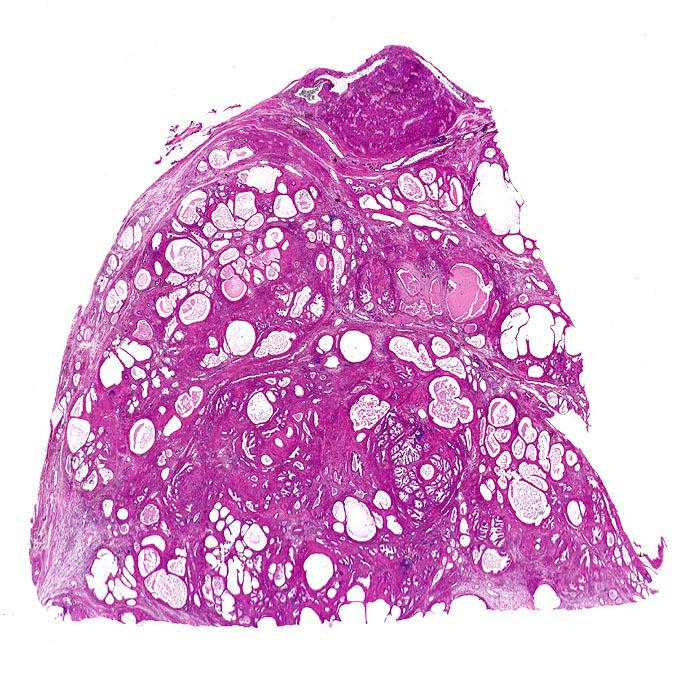

Im Gegensatz zum Prostatakarzinom, welches in der Aussendrüse lokalisiert ist, finden sich die hyperplastischen Knoten vor allem in der Innendrüse. Makroskopisch ist die Prostata meist vergrössert und weist zentral weisse Knoten auf. Die myoglanduläre Prostatahyperplasie ist pathomorphologisch charakterisiert durch eine Proliferation von stromaler und epithelialer Komponente der Prostata im periurethralen Bereich. Die histologische Untersuchung von transurethral reseziertem Gewebe dient dem Ausschluss eines klinisch okkulten Karzinoms.

• Knotiges Parenchym.

• Organoid angeordnete, teils dilatierte grosse Drüsen eingebettet in ebenfalls vermehrtes fibroleiomyomatöses Stroma.